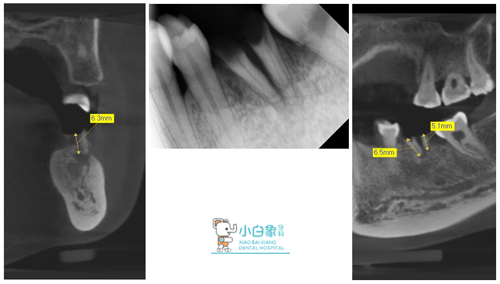

术前 X线 、CT片